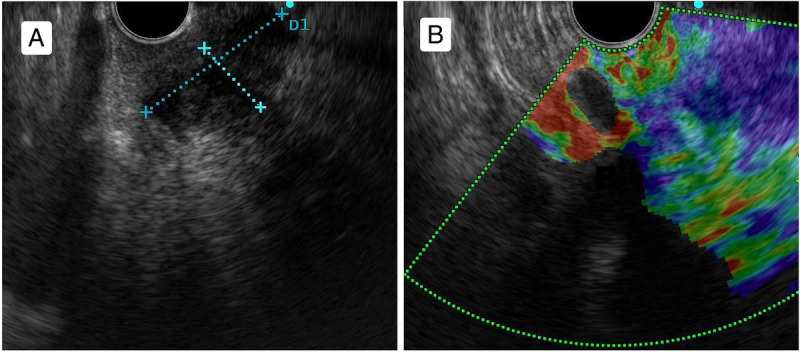

An unusual case of duodenal neuroendocrine tumor presenting with melena diagnosed by EUS-guided fine-needle biopsy.

一例不寻常的十二指肠神经内分泌肿瘤病例,通过胃肠道超声引导下细针活检确诊。